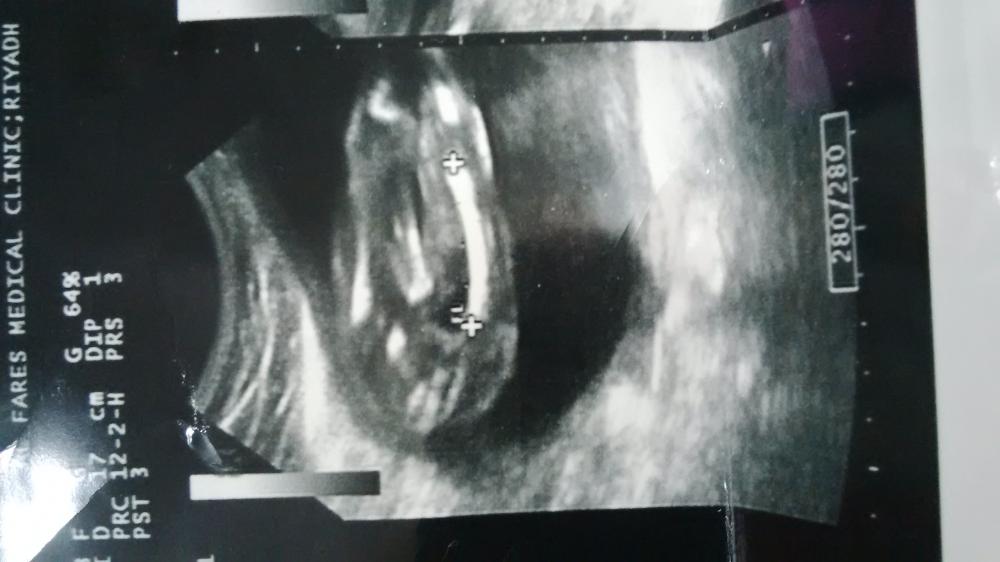

طيب لو عطيتك قياس عظمة الفخذ يكفي ولا لاذم صورة السونار ؟

لان ماعندي صورة معي تقرير وفيه القياسات

كان ع الاسبوع 16 = 18m